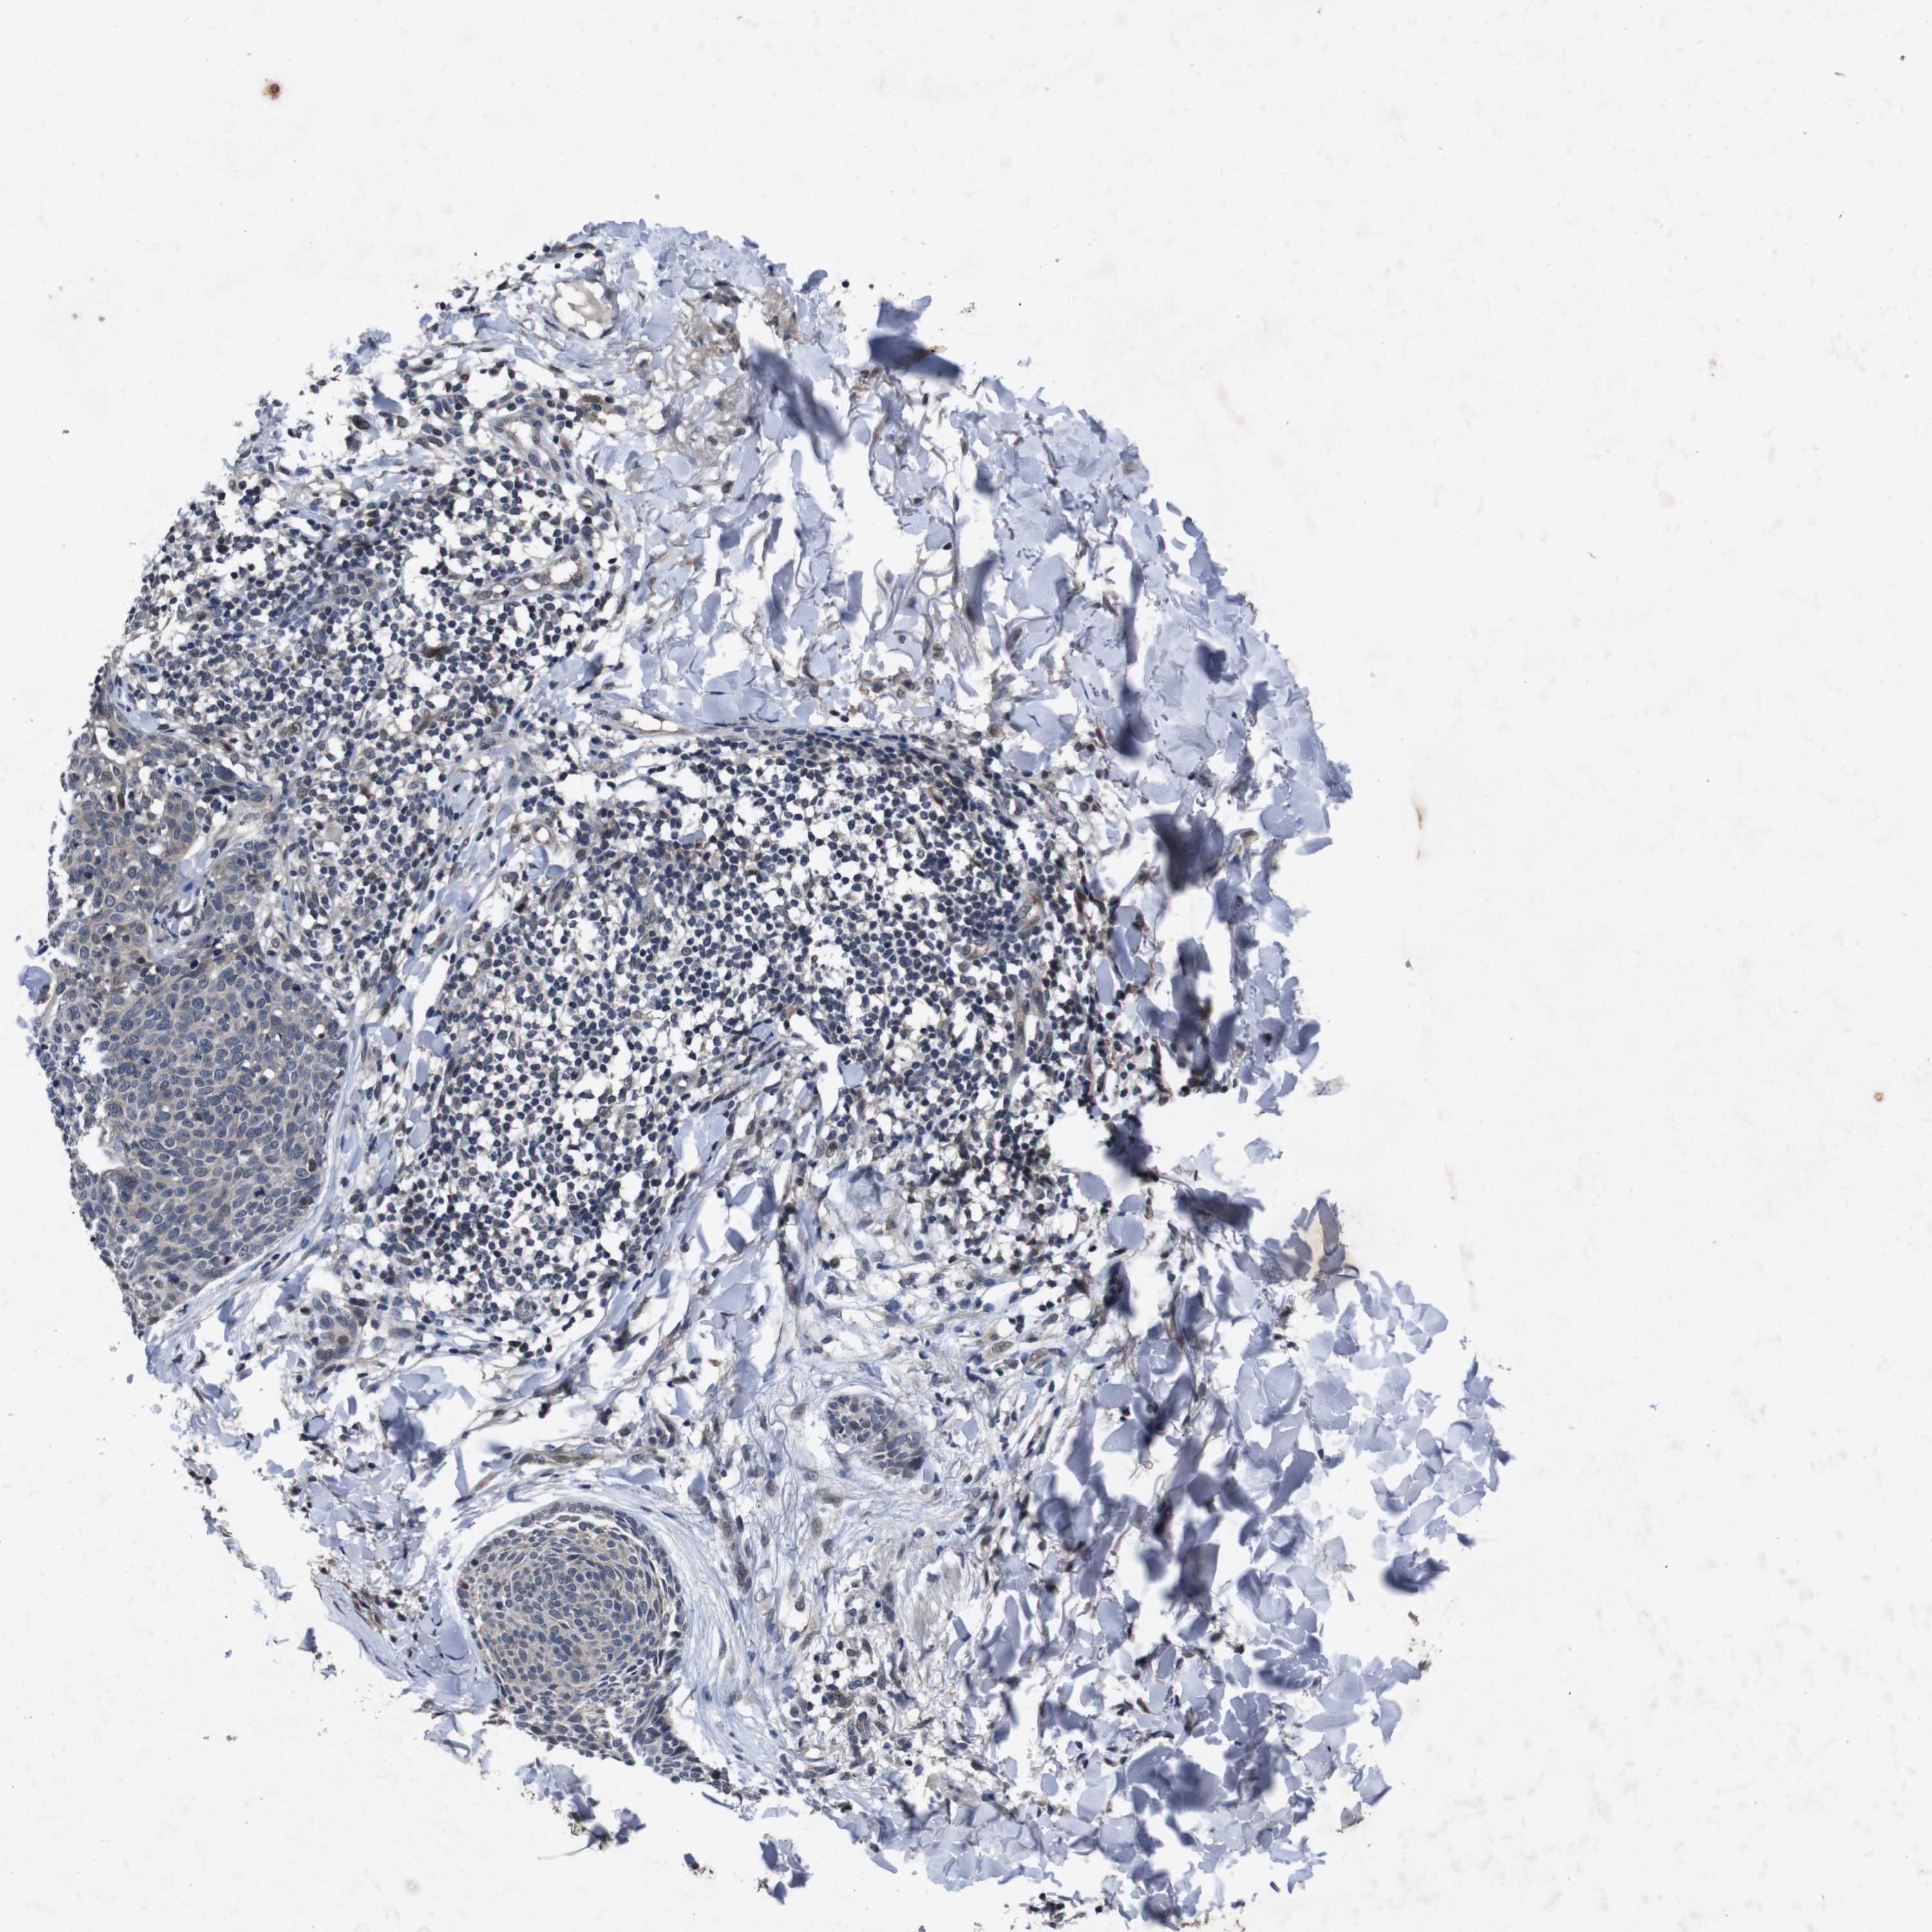

SKIN CANCER - Protein expressioni

A mouse-over function shows sample information and annotation data. Click on an image to view it in a full screen mode. Samples can be filtered based on level of antibody staining by selecting one or several of the following categories: high, medium, low and not detected. The assay and annotation is described here.

Antibody stainingi

Antibody staining in the annotated cell types in the current human tissue is reported as not detected, low, medium, or high, based on conventional immunohistochemistry profiling in selected tissues. This score is based on the combination of the staining intensity and fraction of stained cells.

Each image is clickable and will lead to virtual microscopy that enables deeper exploration of all samples and also displays staining intensity scores, fraction scores and subcellular localization as well as patient and tissue information for each sample.

Antibody HPA026441

Antibody CAB013090

Staining

High

Medium

Low

Not detected

Intensity

Strong

Moderate

Weak

Negative

Quantity

>75%

75%-25%

<25%

None

Location

Nuclear

Cytoplasmic/membranous

Cytoplasmic/membranous,nuclear

Squamous cell carcinoma, NOS